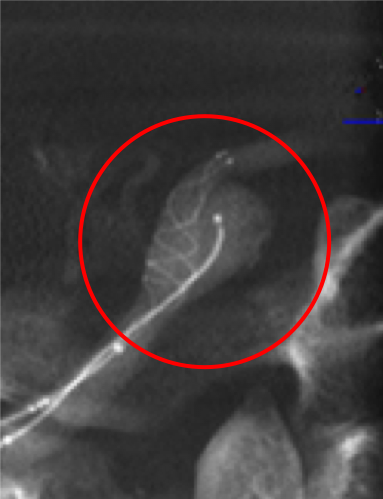

脳動脈瘤コイル塞栓術

脳動脈瘤にマイクロカテーテルという細いカテーテルを挿入し、動脈瘤の中にコイル(プラチナ製の細い糸)を充填して、動脈瘤内に血流が入り込まないようにする治療法です。開頭する必要がありません(低侵襲)。また脳動脈瘤コイル塞栓支援用ステントを使用することで、これまで脳血管内治療が困難であった動脈瘤も治療できるようになってきました。当院では積極的に脳動脈瘤コイル塞栓術を第一選択として治療を行っております。

破裂内頚動脈瘤

術前の造影写真です。〇内に脳動脈瘤が造影されています。

術後の造影写真です。主幹動脈は温存できており、動脈瘤は造影されなくなっています。